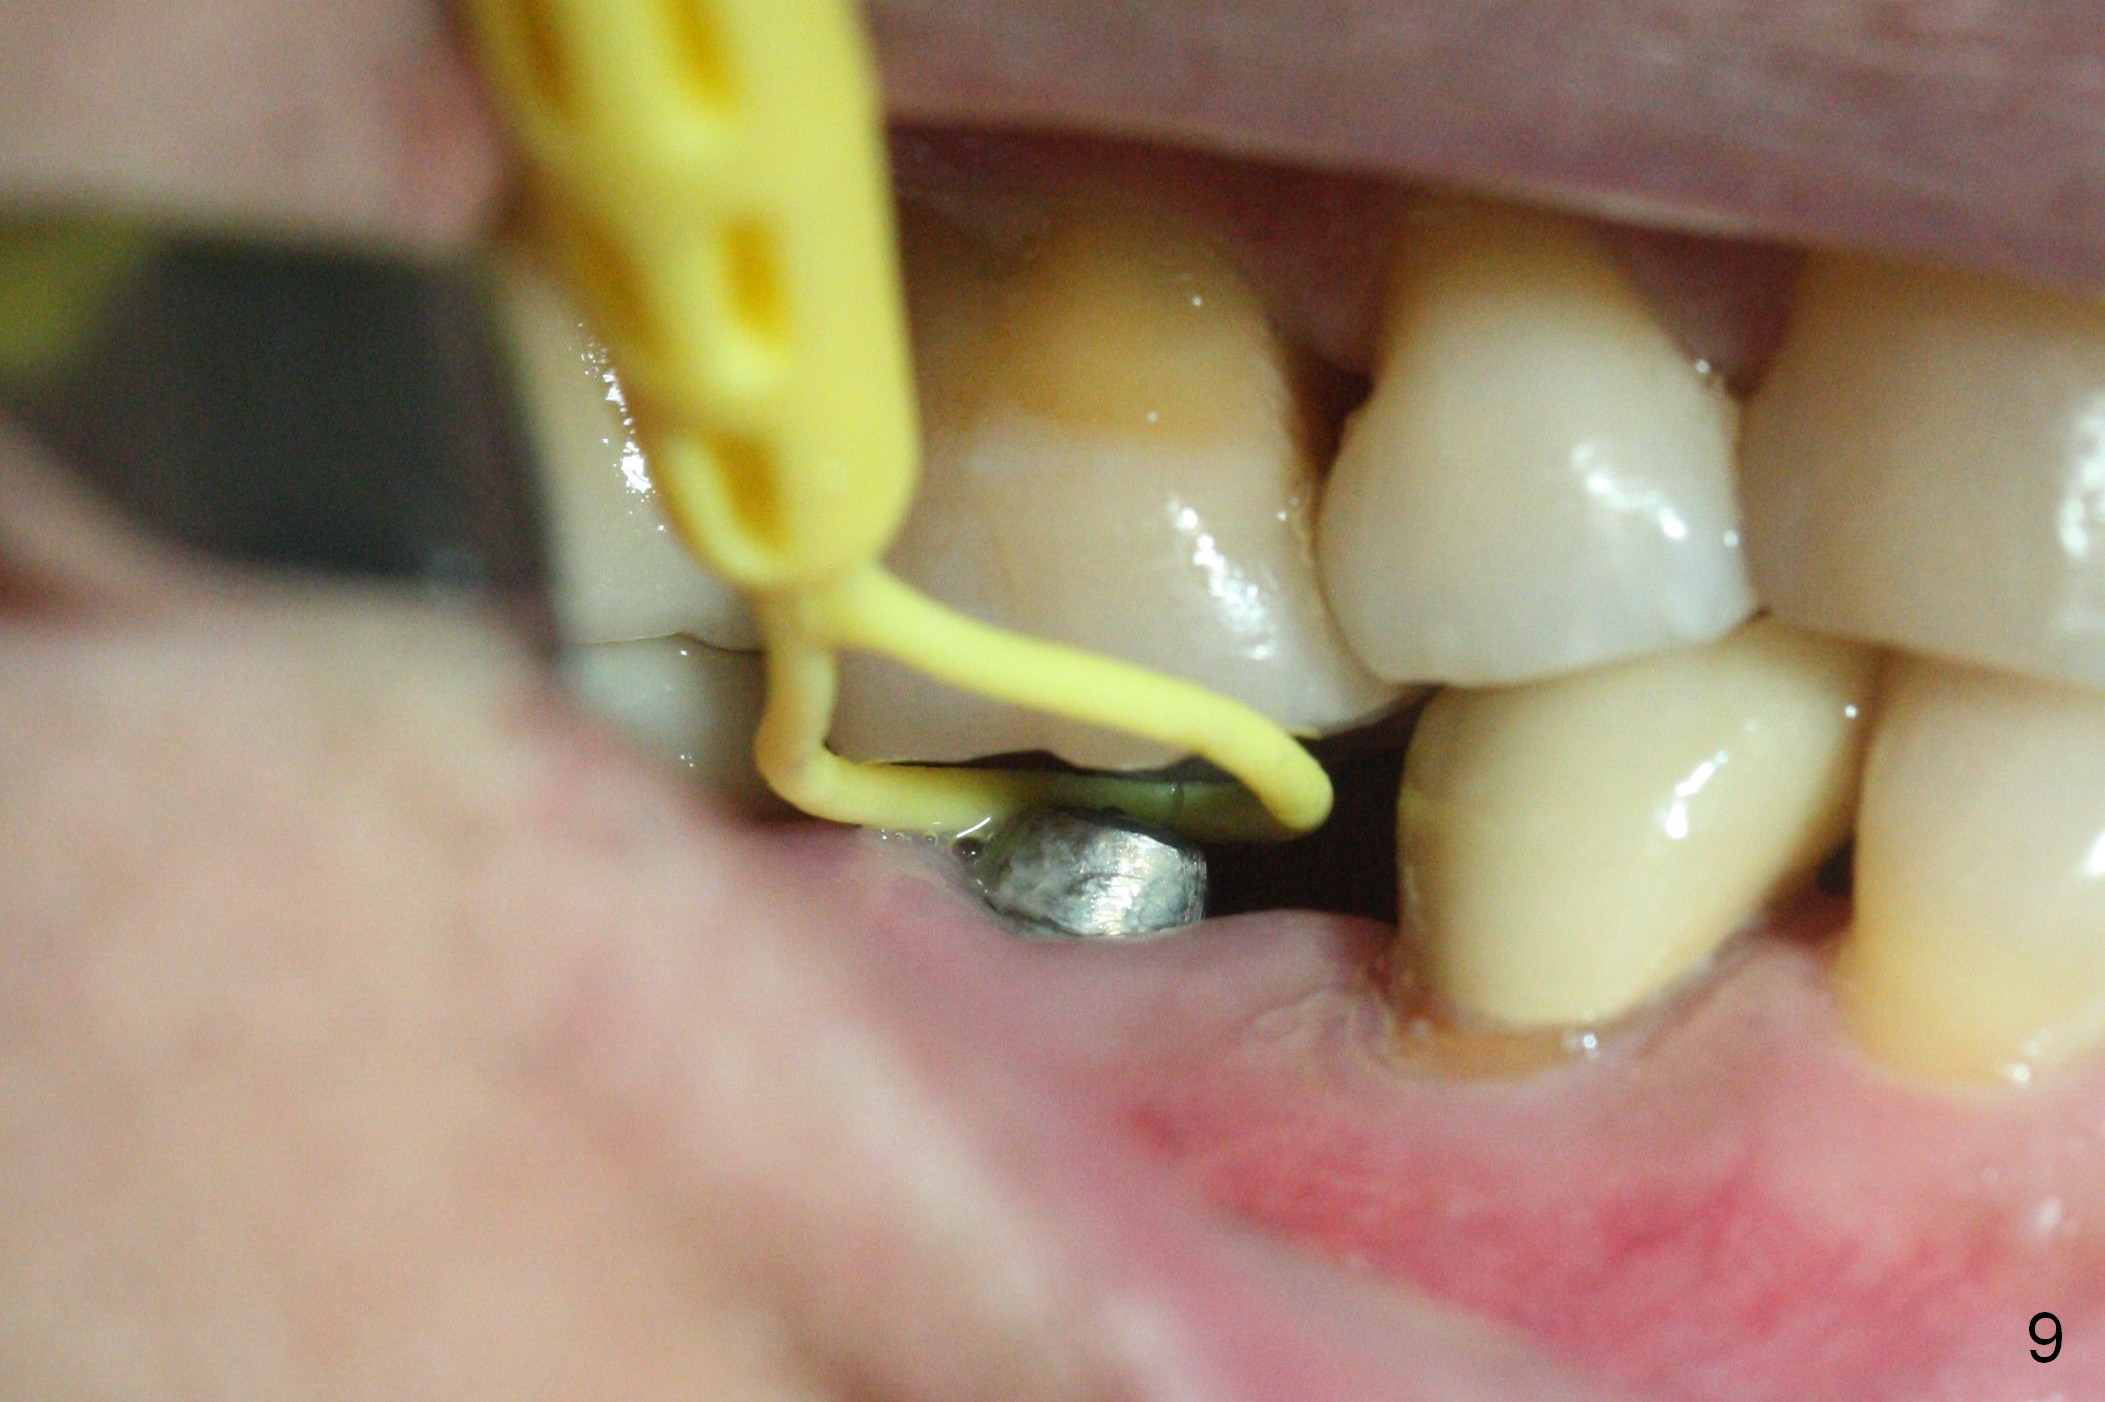

Pre-impression photos show supraerupted #3 (Fig.7). Clearance is a little more than 1 mm between the mesiopalatal cusp of #3 (Fig.7 *) and the rounded abutment (Fig.8). Removal of the abutment turns out to be easy. Reduction is confined to the opposing tooth (slopes of the cusps). No occlusal reduction is done for the new abutment as mentioned above except for 2 retention grooves. One-mm reduction ring barely passes the occlusal clearance (Fig.9). No cement is applied to the abutment in case a longer abutment may be required. Bone density seems to remain the same or increase after cementation of a new crown (Fig.7). The redo crown remains in place 1 year post cementation.